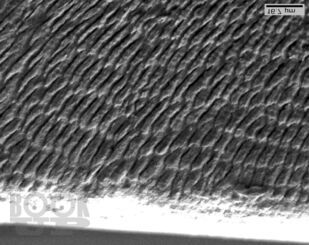

В данном учебном пособии рассмотрены вопросы этиологии, патогенеза, клиники и дифференциальной диагностики клиновидных дефектов зубов, освещены современные подходы к лечению пациентов с клиновидными дефектами твердых тканей зубов, отражена их взаимосвязь с фоновыми заболеваниями организма. В работе представлены научные разработки кафедры ортопедической стоматологии Санкт-Петербургской медицинской академии последипломного образования по изучению морфологического строения и химического состава твердых тканей зубов.